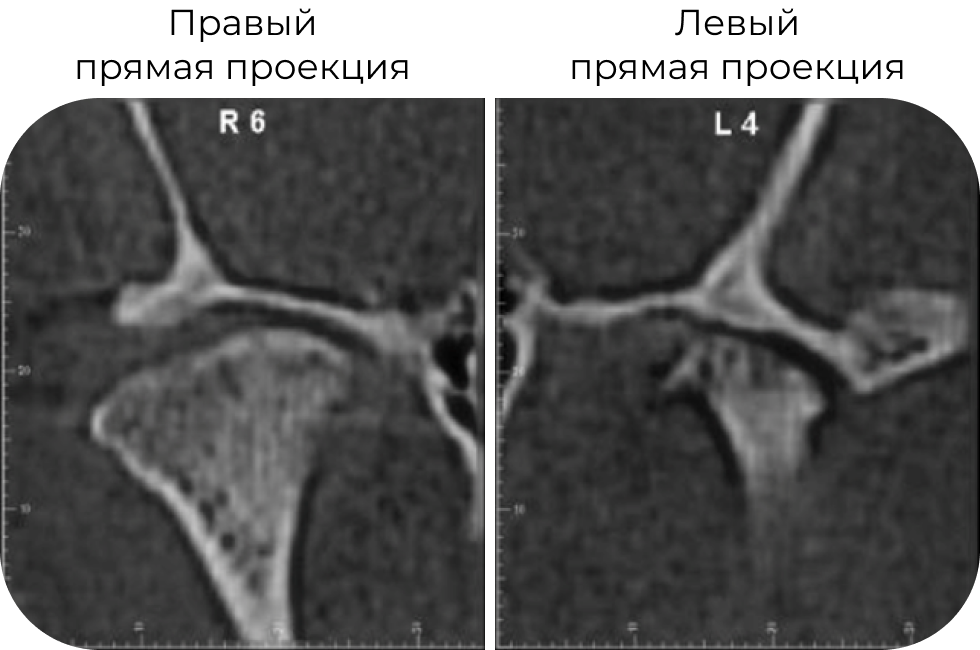

КТ до лечения: начальные признаки фиброзного анкилоза!